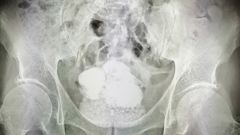

Медики впервые столкнулись с подобным случаем. На рентгене врачи увидели, что мочевой пузырь пациента полностью забит камнями. Самый большой из них достигал 15 см в диаметре.